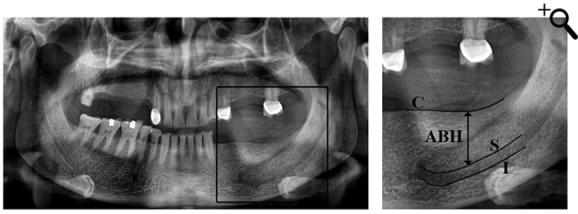

132 cone-beam computed tomography (CBCT) of the edentulous mandibular molar area and dental panoramic radiograph of 508 patients were selected. Exclusion criteria were bone abnormalities and detectable ideal information on each modality. The alveolar ridge morphology was categorized into 7 types according to the relative horizontal location of the alveolar crest to the mandibular canal based on CBCT findings. The available bone height (ABH) was defined as the distance between the upper border of the mandibular canal and alveolar crest. One oral radiologist and one oral surgeon measured the available bone height twice on each modality with a 7-dayinterval.

材料与方法

选取508例患者的无牙下颌磨牙区的132张锥形束计算机断层扫描(CBCT)图像和牙全景放射片。排除标准为骨异常以及每种检查方式中可检测到的理想信息。根据CBCT结果,根据牙槽嵴相对于下颌管的相对水平位置,将牙槽嵴形态分为7种类型。可用骨高度(ABH)定义为下颌管上缘与牙槽嵴之间的距离。一名口腔放射科医生和一名口腔外科医生在每种检查方式上间隔7天测量两次可用骨高度。